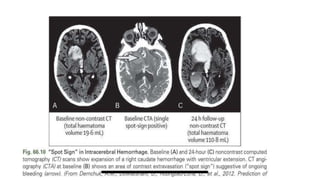

Indicators of Increased HE:

• Anemia

• Anticoagulant-related

hemorrhages

• Identification of a spot

sign on CTA or contrast-

enhanced OR certain

imaging features on

NCCT such as

heterogeneous densities

within the hematoma or

irregularities at its

margins.

Abbreviations: CTA indicates computed tomography angiography; HE, hematoma expansion; ICH, intracerebral hemorrhage; and NCCT, noncontrast computed tomography .

SPOT SIGN

• Spot sign: foci of enhancement

seen within the hematoma on CTA.

• Clinical implication:

Identification of contrast

extravasation and the spot sign are

potent and independent predictors of

hematoma expansion

SPOT SIGN ON CTA BRAIN